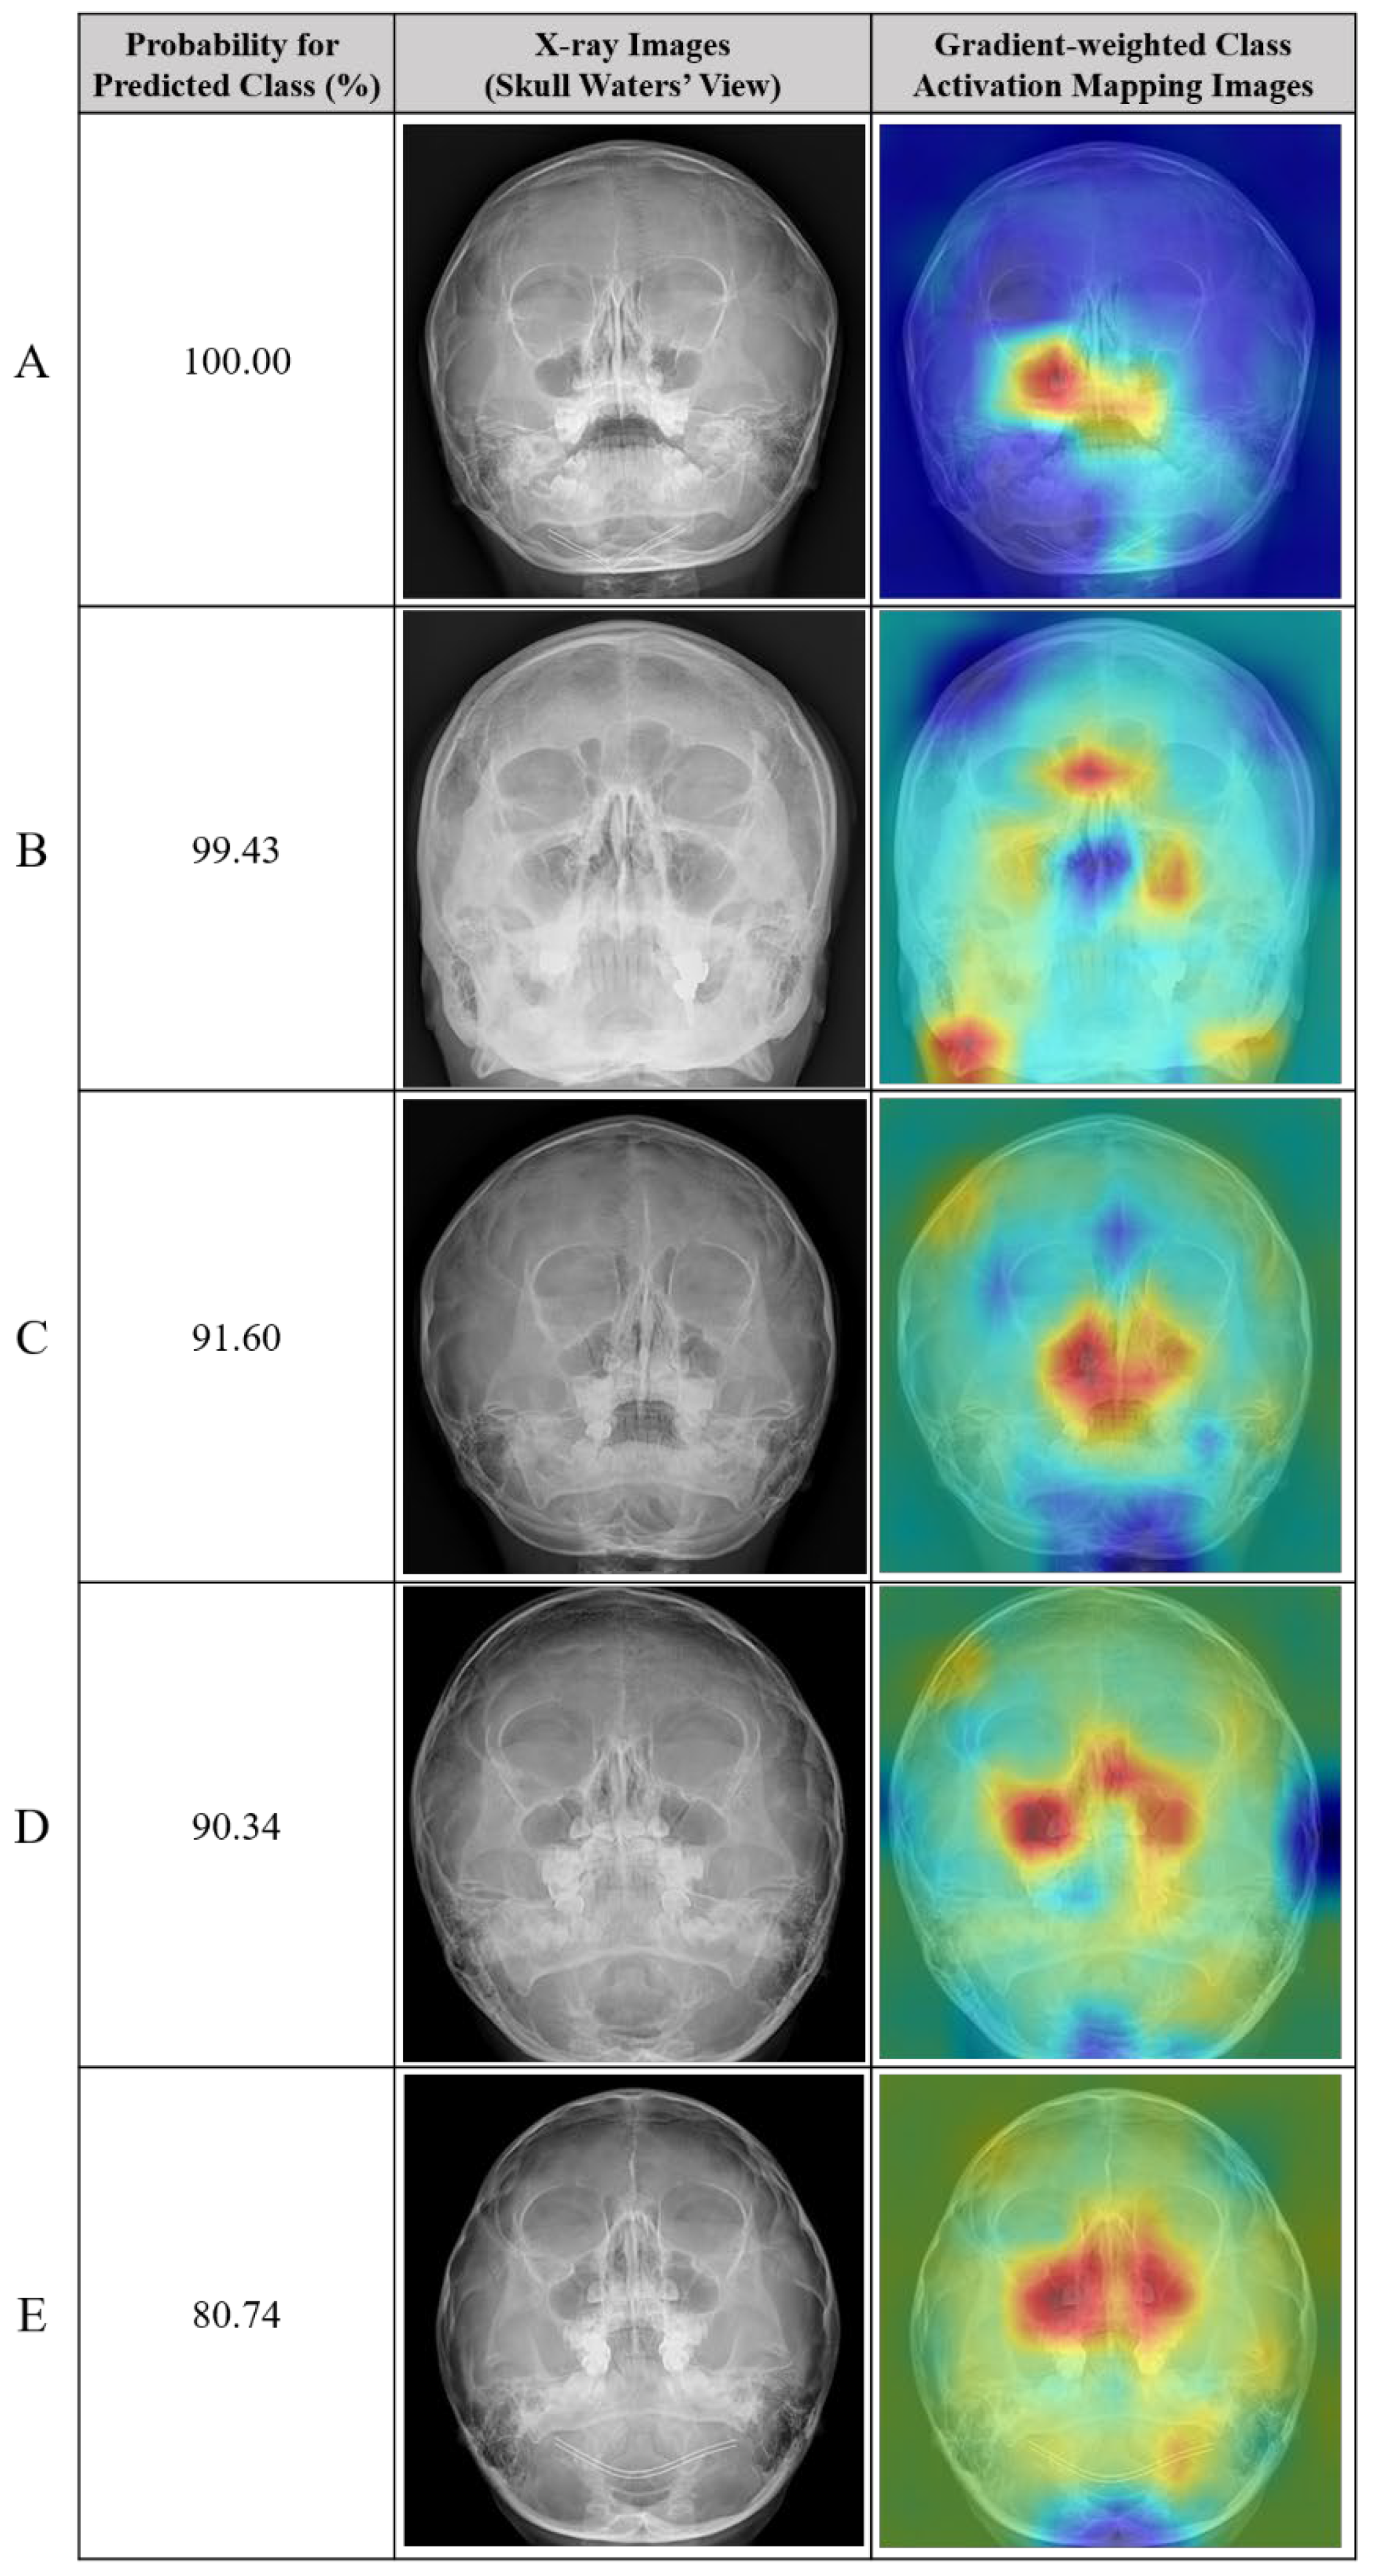

3.3. True Positive and False Positive of Deep Learning Models